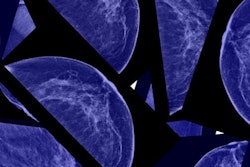

Presenting information to men and women about the "harms" of prostate and breast cancer screening significantly diminishes their interest in screening exams, according to a study published in the January/February edition of the Annals of Family Medicine.

After viewing a video that included information about the limits and harms of each respective screening test, as well as a printed decision aid, the number of men who said they wanted to be screened fell by 36 percentage points, while the number of women who said they wanted to be screened fell by 37 percentage points.

The study presents the results of an evaluation of interventions developed to help patients "consider and trust" the 2009 U.S. Preventive Services Task Force (USPSTF) recommendations on breast screening for women in their 40s, as well as the 2012 recommendations against prostate cancer screening, according to the authors (Ann Fam Med, January/February 2017, Vol. 15:1, pp. 48-55). With respect to breast screening, the USPSTF in 2009 withdrew its recommendation that women in their 40s be screened, advising them instead to make a decision on screening after consulting with their physicians.

| Women who wanted breast screening | 86% | 49% |

| Women who were unsure of breast screening | 6% | 20% |

- Women's desired frequency of mammography changed after being exposed to the material. At the beginning of the study, 54% of women were in favor of annual mammograms and 34% were in favor of biennial exams; after the interventions, 14% were in favor of annual mammograms and 60% were in favor of biennial exams.